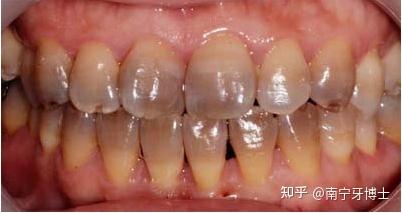

后槽牙牙齿发黑图片,牙齿凹槽上面有黑色

牙齿表面黑色的点或线段就是窝沟龋啦

发黑的牙齿都是蛀牙吗

牙齿凹槽上面有黑色

牙齿边缘发黑图片

龋齿色素沉着区别图片

牙齿根部发黑图片

牙髓坏死牙齿变黑图片